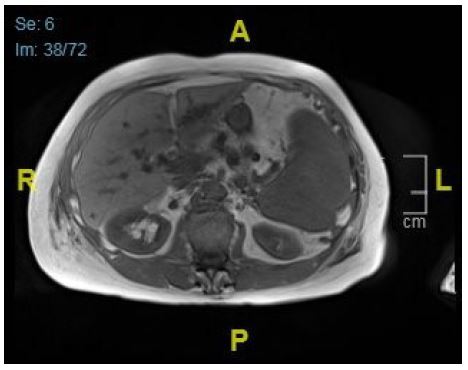

In the second episode, the patient presented septical, with low blood pressure and tachycardia. Elevated cholestatic parameters and liver enzymes were noted, in addition Escherichia coli was found in blood cultures again. CT showed progression of the left bile duct dilatation and an additional enlargement of the common bile duct. MRCP confirmed those findings and for the first time, concretions inside the enlarged left duct and cystic expansions were observed (Figures 3 & 4). SLE was considered as a possible cause of hepatopathy, but antibody diagnostics were negative, and there were no signs of SLE activity. Viral infections were ruled out and the patient had no history of liver disease or alcohol abuse.

Figure 3: Axial T1w-dixon MRI: Progression of cystic formations in the left liver lobe.